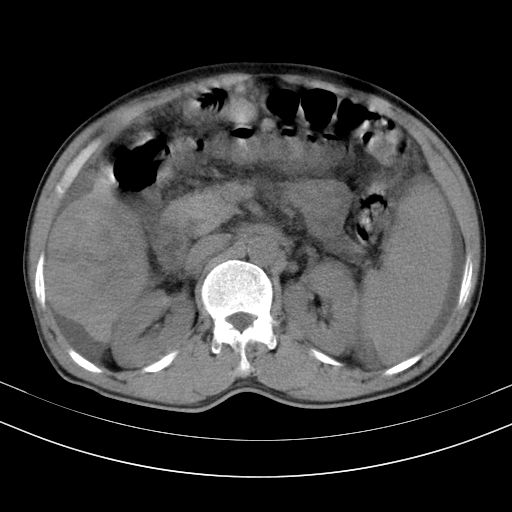

以下是引用随光逐影在2010-2-28 10:23:00的发言:[br]1)考虑肝癌;建议行ct增强扫描检查。2)肝硬化,脾大,腹水。3)慢性胆囊炎。

以下是引用dyqct在2010-2-28 16:44:00的发言:[br][quote]以下是引用随光逐影在2010-2-28 10:23:00的发言:[br]1)考虑肝癌;建议行ct增强扫描检查。2)肝硬化,脾大,腹水。3)慢性胆囊炎。